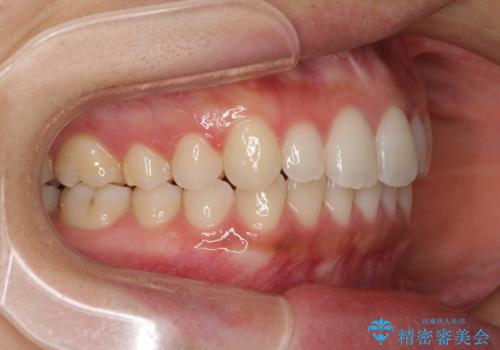

海外勤務中でも矯正治療 インビザラインによる軽度叢生改善

- 前歯のデコボコを気にして来院された患者様です。

治療期間中に海外勤務になる可能性が高いことが分かっていましたが、矯正治療を始めたいとのことでしたので、インビザラインを用いて治療することとしました。

通常であれば半年から10ヶ月程度で終了する歯並びでしたが、海外に長期出張することになったため、1年10ヶ月の期間を要しました。

出張に行かれてしまうと追加のマウスピースを発注できないため、マウスピースの交換頻度を低くし、一時帰国のタイミングに合わせていくことで、スムーズに進めて行くことができました。